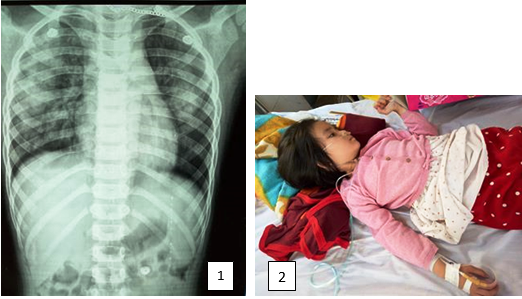

Lúc 16h ngày 15/3/2018, khoa Hồi sức cấp cứu, bệnh viện Nghi Xuân tiếp nhân bệnh nhi Hoàng Linh Đ. 5 tuổi, trong tình trạng tím tái toàn thân, khó thở, vật vã, sùi bọt màu hồng, SpO2: 14%, mạch khó bắt, tim đập nhanh, loạn nhịp, nghe phổi nhiều ran ẩm. Được biết trước đó cháu bị sốt và được truyền dich tại nhà. Khi truyền gần hết chai dịch 500ml, xuất hiện khó thở dữ dội nên gia đình đã đem cháu vào viện. Kíp cấp cứu BS Ngọc, BS Hiếu, cùng các điều dưỡng đã nhận định đây là một trường hợp suy hô hấp cấp do phù phổi cấp nên đã nhanh chóng áp dụng phác đồ cấp cứu phù phổi cấp: bóp bóng có oxy hỗ trợ, lợi tiểu, thuốc morphin để ổn định thần kinh thực vật. Sau 30 phút cấp cứu tích cực cháu đỡ tím tái, tự thở đều, nồng độ oxy máu lên 90%. Sau 3 ngày điều trị tích cực bệnh nhi ổn định, có thể xuất viện trong tuần tới.

Phù phổi cấp do huyết động là một cấp cứu khẩn trương, nếu phát hiện chẩn đoán sớm, can thiệp kip thời, chính xác, bệnh có khả năng phục hồi nhanh. Nếu không can thiệp kịp thời và đúng sẽ nhanh chóng suy hô hấp năng và nguy cơ tử vong rất cao. Thành công của kíp cấp cứu thể hiện trình độ chuyên môn vững vàng của các BS HSCC - Nhi, sự phối hợp nhịp nhàng của cả e kíp giữa BS và Điều dưỡng. Ngay sau đó BGĐ đã quyết định thưởng nóng cho kíp trực cấp cứu.

Ảnh: Hình ảnh phổi mờ hình cánh bướm do phù phổi cấp của bệnh nhi Đ (Ảnh 1). và cháu Đ. sau khi cấp cứu ổn định (Ảnh 2)